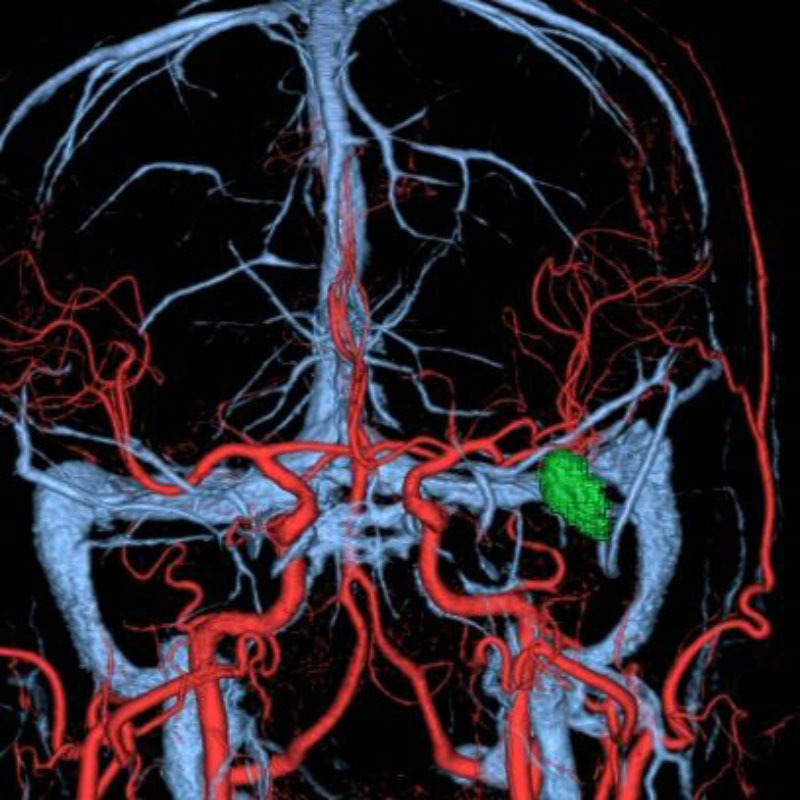

脳動静脈奇形

摘出術

南田/野本/古谷/元永